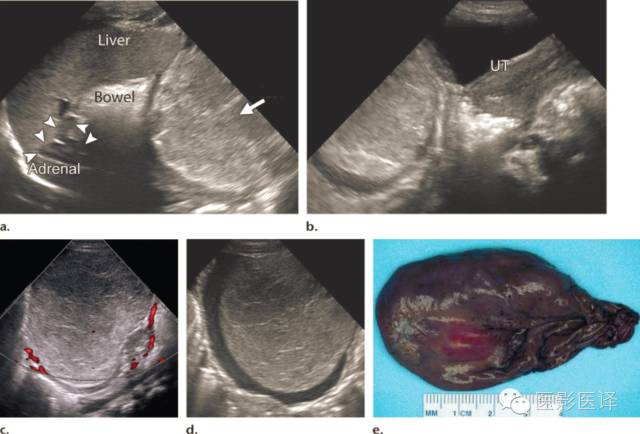

图6.出血性梗塞导致了卵巢囊肿的实性表现。(a、b)新生儿生后第一天矢状位超声图像显示一个回声团块(a箭),向上推挤充气的肠管。团块与肝脏、肾上腺及子宫(UT)独立。A中的箭头是右侧肾上腺。(c)彩色多普勒超声图像显示团块内无血流。(d)轴位超声图像显示团块从边缘开始凝缩,是确认广泛出血性坏死的征象。(e)切除的卵巢大体照片显示广泛出血性梗死,符合扭转的表现。